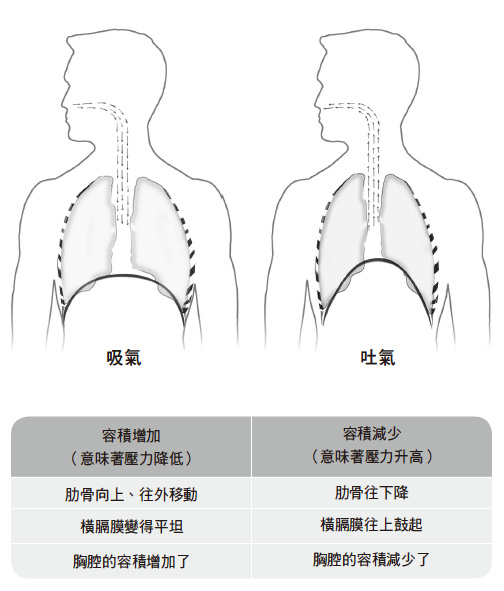

◆吸气

肺脏装在一个囊里面,这个囊称为「胸膜」,它具有足够的弹性,让海绵般的肺脏可以顺利膨胀、收缩。把横膈膜的运作方式重新回想一遍,你对呼吸机制的了解就会再深入一些。

吸气的时候,横膈膜收缩起来,这时候它会下降,推挤它下方的腹腔器官。胸腔的体积变化造成胸膜内部出现部分真空,此时外面的空气会立刻迅速流入体内,填补这部分的真空。同一时间,肋骨会向上、往外移动,为膨胀起来的肺脏创造更多空间。

◆吐气

在呼吸的这个阶段,空气会从肺脏排出。吐气时,横膈膜会松弛下来,向上移动,造成胸腔内部的气压跟外界的气压出现差距。简而言之,这条呼吸肌改变了胸腔的体积,交替制造出低压和高压的区域,使得空气被灌入或是排出肺脏。当横膈膜随着吐气而松弛时,它的形状变得如同一座圆顶巨蛋;与此同时,肋骨也往下、往内移动,造成胸腔的形状改变,于是胸腔本身和胸膜内部的空间都缩小了。在这个阶段中,空气快速从肺脏排出,以便体内的气压跟外界的气压平衡起来。

以上所说的一切都是自动发生的,完全不劳我们费神去呼吸,这一点很重要,请务必要了解。当横膈膜、肺脏、腹腔、胸腔周围的所有肌肉全部运作得很和谐时,呼吸便可以达到最佳效能。